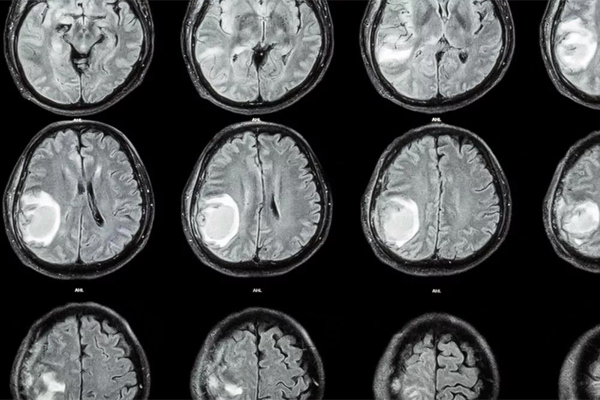

Nghiên cứu dẫn đầu bởi bác sĩ thần kinh học Zongze Li từ Phòng thí nghiệm Peng Cheng (Thâm Quyến - Trung Quốc) cho biết bệnh nhi giấu tên được kiểm tra bằng CT scan khi có những dấu hiệu chậm phát triển thần kinh vận động, đầu to lên bất thường, ứ dịch.

Các hình ảnh cho thấy một khối u lạ xuất hiện trong não đứa trẻ, được xác định là một bào thai vì có cột sống và hai chương chân, cũng như cho thấy thai nhi đó là một thai bị dị tật nứt đốt sống. Thai nhi cũng đã phát triển một chồi chi trên và cấu trúc giống ngón tay.

Hình ảnh CT scan đầu của đứa trẻ 1 tuổi - Ảnh: NEUROLOGY